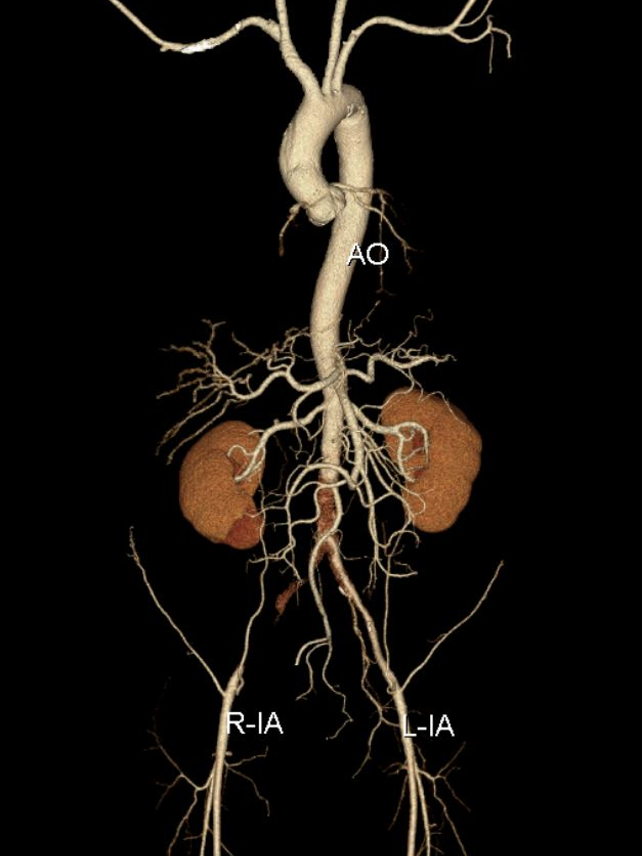

患者特征:64岁男性,Rutherford 3级(间歇性跛行),TASC D级病变。

治疗策略:复合手术(双侧股动脉切开取栓 + CERAB),兼顾血栓清除与长期血管重建。

左侧肱动脉入路,主髂动脉造影